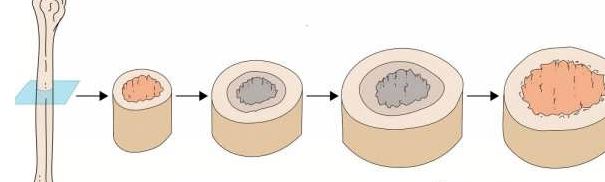

مرکز اولیه استخوانسازی: در وسط استخوان (دیافیز) شکل میگیرد.

مرکز ثانویه استخوانسازی: بعدها در دو سر استخوان (اپیفیز) ایجاد میشود.

در این فرآیند، سلولهای غضروفی میمیرند و جای خود را به حفرههایی میدهند که توسط «استئوبلاستها» (سلولهای استخوانساز) پُر میشوند. این سلولها شروع به تولید بافت سخت استخوانی میکنند.